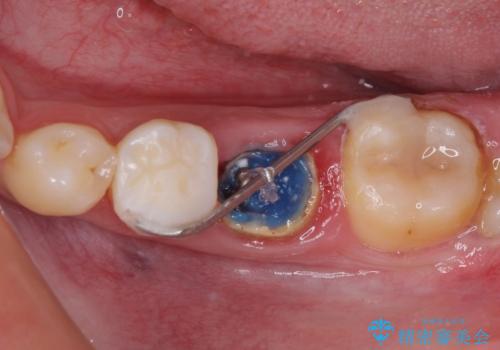

- クラウンを装着したばかりの歯の歯肉が腫れていることを気にして来院された患者様です。

むし歯がとても大きく、歯茎に歯の一部が埋もれてしまっているため、汚れが溜まりやすくなっている状態でした。

根歯の挺出(歯を引っ張り出す部分矯正)、歯周外科処置などを行った後、オールセラミッククラウンにて補綴することとしました。